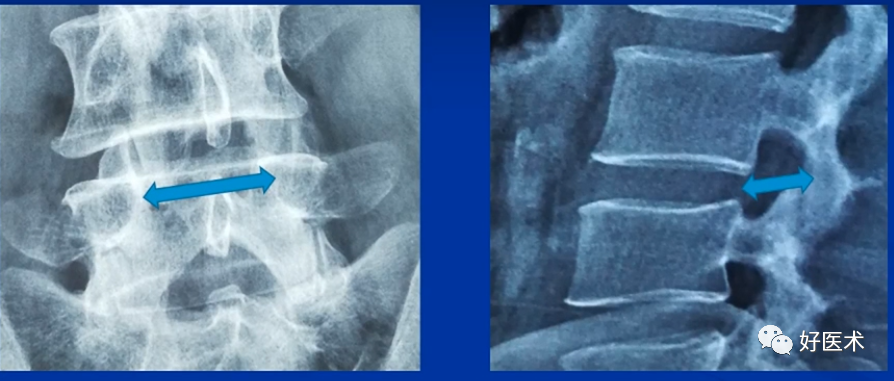

透视腰椎正位:上下终板成单边;椎弓根(猫眼)对称;棘突居中。

透视腰椎侧位:上下终板成单边;椎弓根上下缘单边;椎体后缘成单边。

实际情况:没有专业的手术透视工作人员;正位和地面垂直;侧位和患者垂直;正位看猫眼内外,侧位看椎弓根上下。

判断:透视正位,椎管外的长度设定为A;透视侧位,椎体外的长度设定为B;如果A大于或者等于B,定位针不在椎管内;如果A明显小于B,定位针在椎管内。

透视结果(优秀):①正位:定位针在猫眼内;②侧位:定位针在椎弓根正中,和椎体轴向平行;③目标椎体正确。

透视结果(及格):①正位:定位针突破猫眼内缘;②侧位:定位针在椎体内,方向和轴线不平行,预计椎弓根螺钉不会突破椎体;③目标不明确。